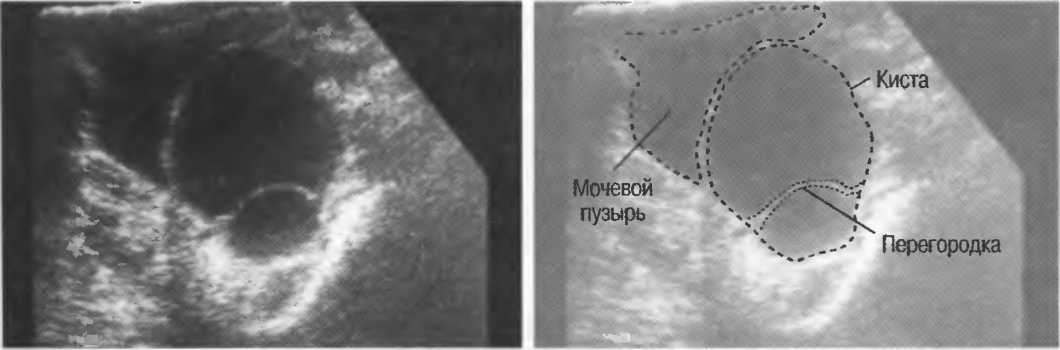

Кисты

Киста, как правило, визуализируется в виде анэхогенной зоны, при этом структуры, расположенные за кистой, обычно усилены: полость кисты анэхогенна, поскольку в ней нет структур с различным акустическим сопротивлением. В результате того что жидкость не поглощает ультразвук в такой же степени, что и ткань, эхо-сигналы от расположенных позади кисты структур гиперкомпенсированы сканером и выглядят усиленными — появляется эффект усиления задней стенки (рис. 14а,б).

Киста определяется в виде анэхогенной зоны с усилением по задней стенке. Если в кисте есть внутренние зхоструктуры, то они могут быть реальными или являться артефактами.

Структура, наподобие содержащей чистую жидкость кисты, визуализируется как анэхогенная зона. Стенки кисты отражают ультразвуковые сигналы под углом, и информация не поступает назад в трансдьюсер. В результате этого появляются боковые тени, но сзади кисты имеется усиление эхосигналов (усиление задней стенки) (рис. 15).

Артефакты могут определяться в любой кистозной структуре (такой, например, как мочевой пузырь или желчный пузырь) и чаще определяются ближе кпереди, становясь менее выраженными на глубине. Они исчезают или меняют свой характер при изменении положения датчика. Но истинные структуры в кисте, такие как перегородки, сохраняют свое местоположение независимо от положения датчика. Истинные отражения имеют место при наличии сгустка крови, гноя, некротической взвеси, и все это чаще визуализируется по задней стенке: если эти структуры не фиксированы к стенке, они изменяют свое положение при перемене положения тела пациента (рис. 16).

Рис. 16а. Злокачественная киста яичника: крупная киста с внутренней перегородкой, которая остается в прежнем положении при сканировании пациентки в различных положениях.

Осадок в кисте может флотировать, формируя уровень, изменяющий свое положение при перемещении пациента (рис. 16б,в).

Рис. 16б. Киста с усилением по задней стенке, латеральными тенями и осадком в полости.

Рис. 16в. Этот же пациент, что и на рис. 16б. Сканирование осуществляется в разных положениях больного. Уровень, создаваемый осадком, смещается.